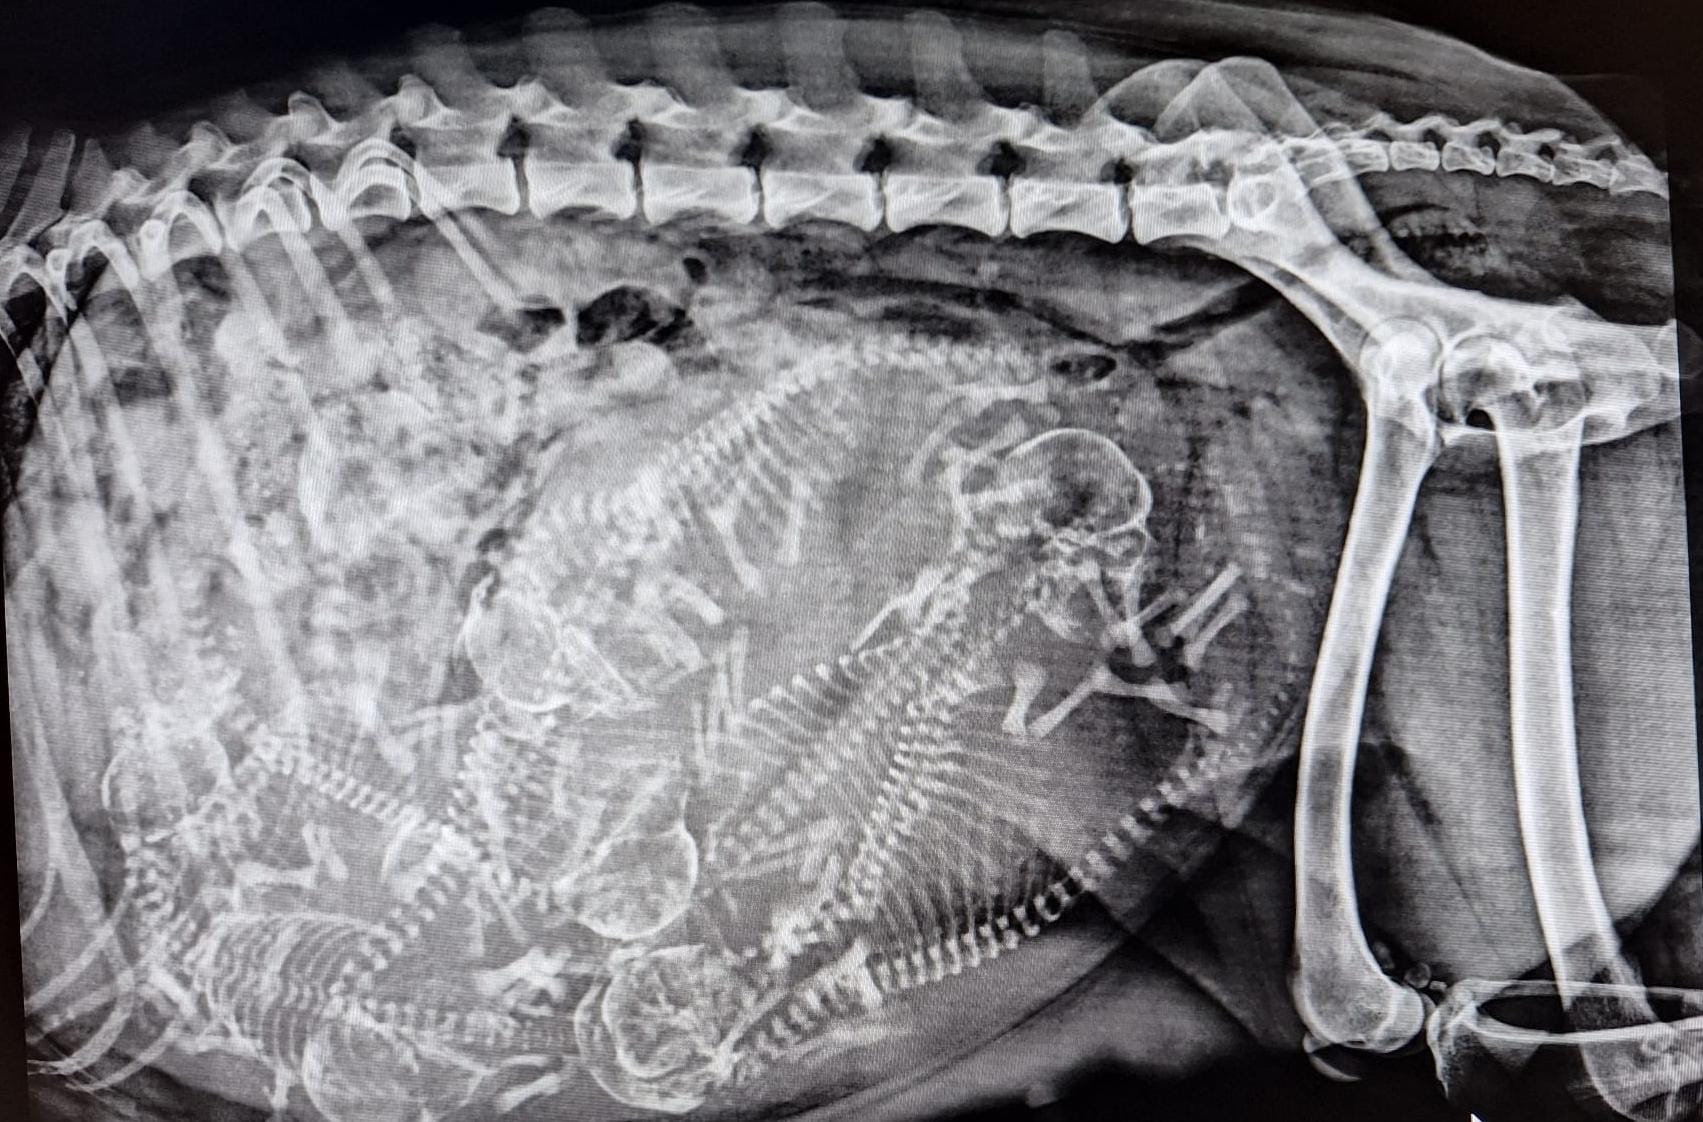

Röntgen

Geburt